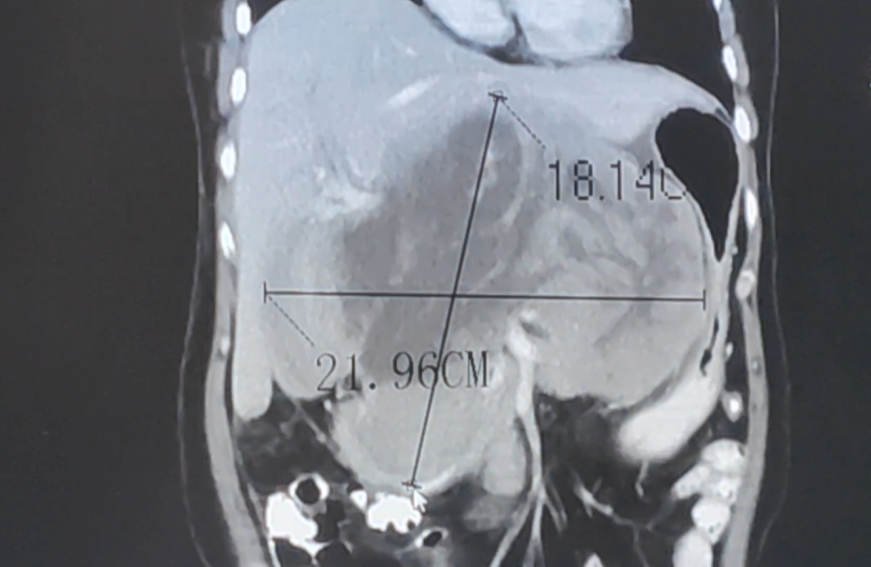

汪姐并没有放弃,她的爱人一直积极寻找肿瘤专科医院,寻找新的治疗希望。经多方打听,最终于2024年7月来到国家临床重点肿瘤专科医院——广州复大肿瘤医院就诊。当时入院的她根本吃不下东西,一吃东西就抱着盆呕吐起来。其增强CT显示肿瘤已经长到22公分左右,并且压迫到胃,导致胃腔变小。

▲2024年7月治疗前